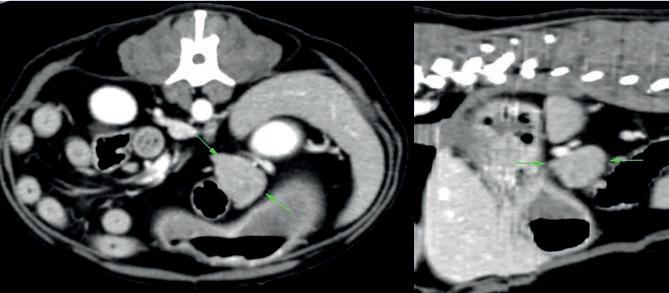

EN EL QR PODRÁS DESCARGARTE TODO EL MATERIAL DE LA CAMPAÑA 2024 NECESARIO PARA REDES SOCIALES:

• Contenidos editables para personalizar la campaña en tus redes sociales con adhesivos para tus reels, post, stories y WhatsApp, además de una guía de publicaciones,

• Guía práctica con nuevas ideas y consejos para elaborar post atractivos que enganchen